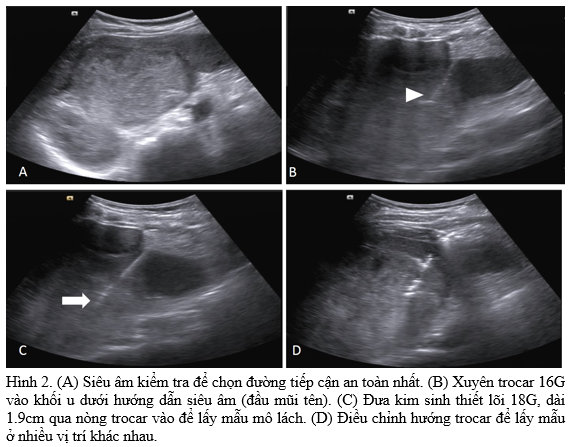

- Gây tê tại chỗ dưới da, bao lách và đường hầm bằng Lidocain

- Chọc kim trocar 16G vào tổn thương dưới hướng dẫn siêu âm. Chúng tôi thường sử dụng đầu dò cong với tần số 3.5MHz và hướng chọc kim theo chiều dọc của đầu dò để kiểm soát tốt đường chọc và đầu kim. Nếu có nhiều tổn thương, ưu tiên tổn thương ở ngoại vi, đường chọc ngắn nhất và qua nhu mô lách ít nhất.

- Rút nòng trocar, đưa kim sinh thiết 18G, lõi 1.9cm vào lấy mẫu nhiều vị trí.

- Nút tắc đường hầm bằng Gelatin sponge cắt nhỏ, kích thước # 1x1mm.

- Rút trocar

- Siêu âm kiểm tra

Bệnh nhân nữ 64 tuổi, vào viện vì đau vùng hạ sườn trái. Chụp cắt lớp vi tính ghi nhận lách lớn, trong nhu mô có nhiều khối choán chỗ bờ không đều, giới hạn khá rõ, đẩy lồi bao lách, chèn ép các tạng lân cận nhưng chưa thấy rõ xâm lấn (Hình 1). Khối lớn nhất có kích thước #10.5x10x9.5cm, trung tâm có hoại tử. Các khối này ngấm thuốc kém qua các thì. Vài tổn thương nhỏ tương tự ở gan, kích thước 7-15mm. Không phát hiện thêm bất thường nào khác. Bệnh nhân được chỉ định sinh thiết lách (Hình 2). Vì nguy cơ chảy máu khi sinh thiết lách, chúng tôi quyết định sử dụng kỹ thuật kim đồng trục có nút tắc đường hầm (Hình 3). Sau sinh thiết bệnh nhân đau tức nhẹ ở vùng hạ sườn trái, huyết động ổn định, không có tai biến tức thì và biến chứng muộn. Kết quả giải phẫu bệnh là angiosarcoma lách.